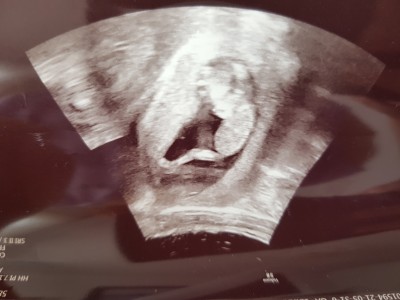

Kızlar usg 12 haftalık tahmin yapabilir misiniz rica etsem

Gebelik haftası 14

Erkek geldi içimden ogrendin mi canim :)

Erkek sanırım doktor ne dedi sana